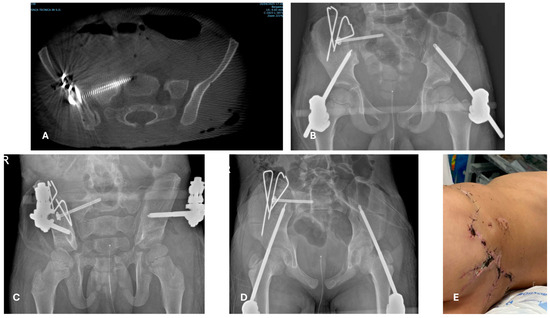

4.2. Is a Temporary Damage Control Surgery (DCO) Indicated?

4.3. Does the PPT/PMT Patient Need a Different Treatment Method Because of His/Her General Conditions?